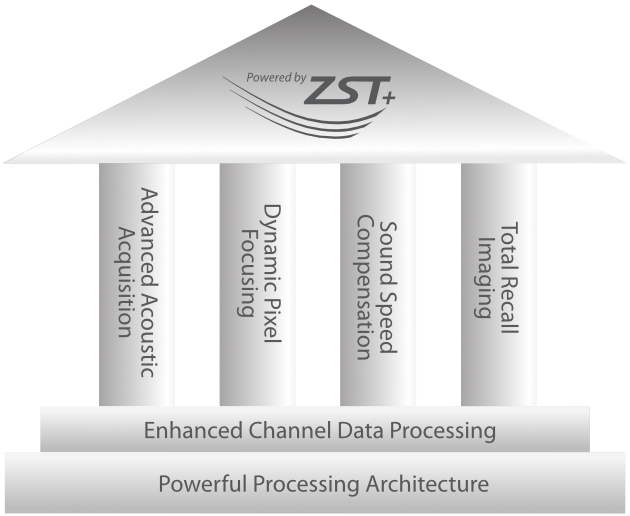

Com tecnologia ZST+

A plataformaZST+ representa um salto extraordinĂĄrio na tecnologia de ultrassom, passando da tradicional forma??o de feixe para o processamento de dados de canal. Essa inova??o revolucionĂĄria supera as compensa??es tradicionais entre resolu??o espacial, resolu??o temporal e uniformidade do tecido, resultando em uma qualidade de imagem inigualĂĄvel com infinitas solu??es de gera??o de imagens.